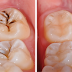

3. Loại bỏ mô răng bị sâu

Bác sĩ sử dụng thiết bị nha khoa chuyên dụng nạo vét hết những mô răng đã bị sâu nhằm ngăn chặn sự lây lan của bệnh lý. http://matdanrangsuveneer.com/tong-hop-nhung-nguyen-nhan-rang-thua.html